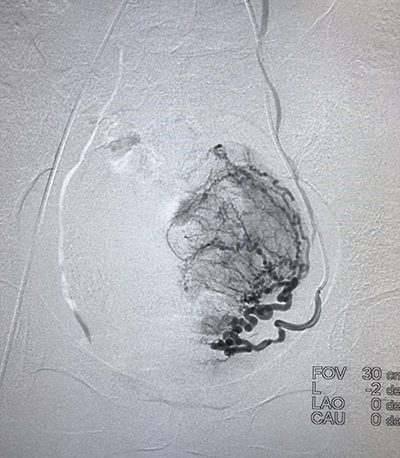

![]() | ![]() |

| (肺癌的介入治疗) | (盆腔恶性肿瘤的介入治疗) |